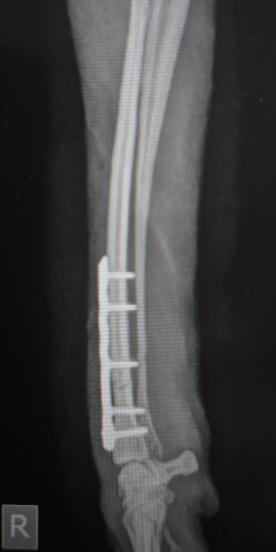

Postoperatives Röntgenbild: die Fraktur wurde reponiert und mit Platte und Schrauben stabilisiert (Osteosynthese).